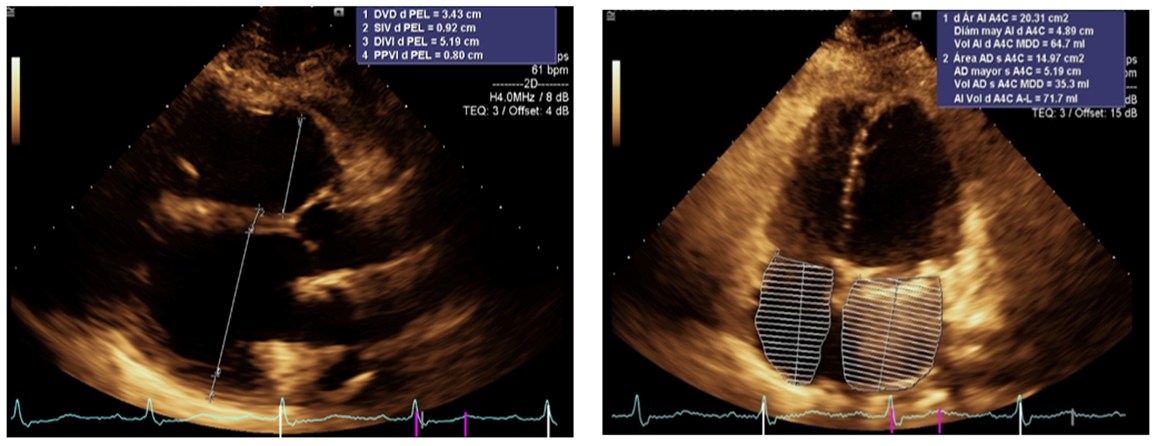

Figure 3: Apical 4-chamber axis showing dilation of the left atrium

Figure 4: Apical 2-chamber axis showing the ejection fraction and end-diastolic volume of the left ventricle, the acoustic shadow generated by the mechanical mitral prosthesis is observed (red arrow)